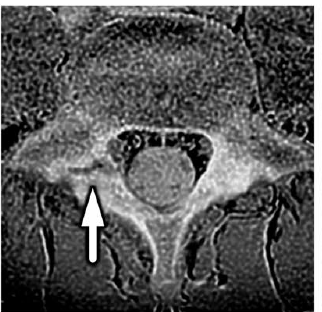

図2: 腰椎分離症のMR画像(画像は腰椎の水平断面を示す。矢印は腰椎分離症の病態箇所である)

本研究は「片側腰椎分離症の選手には、どのような体幹筋の形態と機能の特徴があるのか」を、画像(MRI)と簡便なスクリーニングテストの両面から整理することを目的としました。対象は同一クラブに所属する12〜14歳の男子サッカー選手107名です。全員に3テスラ※6MR装置を用いて腰部の撮像を実施し、片側腰椎分離症が確認された19名を抽出しました。比較のため、年齢・身長・体重が同程度になるように対照群19名を設定しました。

MRIでは、腰椎L4/5レベルの画像から体幹の主要筋(大腰筋、多裂筋、脊柱起立筋)の断面積を左右別に測定しました。さらに、現場で実施しやすい2つの簡便なスクリーニングテストを行いました。1つ目は仰向けで片脚を上げるActive Straight Leg Raise(脚上げテスト)で、脚を上げた側の骨盤が沈む現象の有無を確認しました。2つ目はうつ伏せで脚を上げる股関節伸展テストです。

その結果、片側腰椎分離症の選手では、分離症側の大腰筋が対照群より小さく(約12%)、左右差が認められました。一方で、多裂筋と脊柱起立筋には明確な差がみられませんでした。さらに、ASLRで「腰椎分離症側の骨盤が沈む」現象は腰椎分離症を有する選手に多く、ASLRが陽性だった16名のうち13名が片側腰椎分離症を有していました。これらは、片側腰椎分離症では「深部筋(大腰筋)の左右差」と「脚上げ動作での骨盤の安定性低下」がみられる可能性を示します。